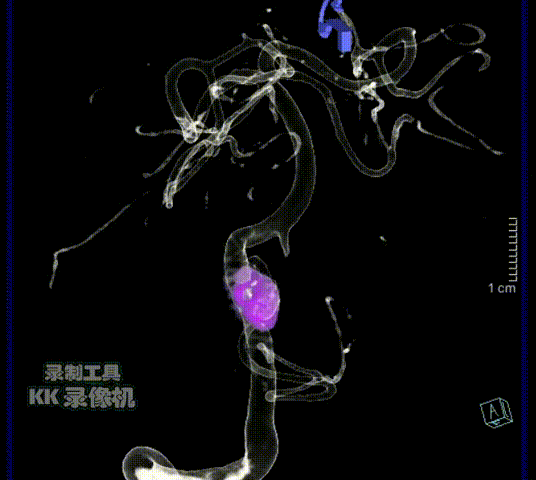

造影显示左侧椎动脉非优势侧

(5F造影导管即造成造影剂的滞留)

右侧椎动脉造影证实V4段夹层动脉瘤

(可见内膜瓣/瘤内造影剂滞留)

3D造影:动脉瘤处有明显的凹陷,符合夹层内膜瓣表现;PICA从动脉瘤远端发出,动脉瘤大小约6.5×12.8mm,受累椎动脉直径约4.3mm,覆盖远近端达正常血管约需30mm支架长度。

术后12个月复查DSA,右椎动脉术后改变,无复发。停用阿司匹林。